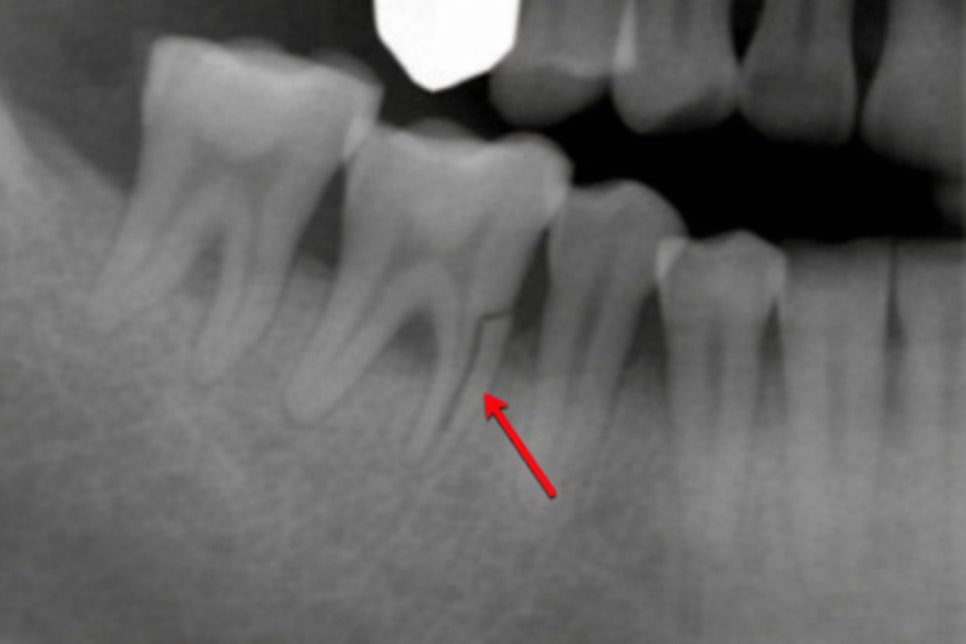

뿌리까지 이어진 수직 파절

수직 치근 파절은 치과에서부터

치근까지 세로 방향으로 금이 간 상태를 말합니다.

대개 신경치료를 받은 곳에서

발병률이 높게 나타나는데,

근관 충전 후 치아는 수분을 잃고

취약해진 상태이기 때문에

외부 충격이나 저작압에 의해

수직으로 파절되기 쉽습니다.

균열 틈새로 세균이 침투하면

치근단 범위까지 감염이 확산되고

이 과정에서 치아를 지탱하는

치조골 손실이 발생하게 됩니다.

치조골은 한 번 손상되면

회복이 어렵기 때문에

진단이 늦어질수록 주변 조직 전반에

피해가 커질 수 있습니다.

수직 치근 파절은 치료를 시도하더라도

예후가 불량할 때가 많습니다.

치조골 파괴가 심해지면 추후

임플란트 식립조차 어려워질 수 있기 때문에

빠른 발치가 권장되는 경우가 많습니다.

잔존 치조골 상태에 따라

치료 방향이 달라질 수 있으므로

정밀 진단 후 결정하는 것이 중요합니다.